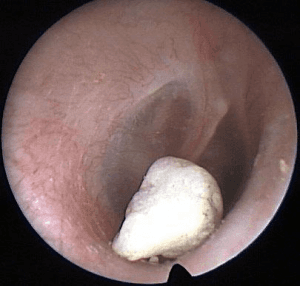

Įstrigęs sieros kamštis

Pakitusios liaukos, išsidėsčiusios klausomosios angos viršutinėje sienelėje, išskiria ausies sierą (lot. cerumen), kuri apsaugo ausį, kad į ją nepatektų pašalinių medžiagų, tokių kaip oro teršalai, saugo išorinę klausomąją landą nuo sužalojimų. Sveikoje ausyje susidariusi siera, epidermio sankaupos savaime pasišalina kramtymo metu. Veikiant įvairiems veiksniams siera iš ausies visiškai nepasišalina ir kaupiasi išorinėje klausomoje landoje, ilgainiui suformuodama sieros kamštį. Dažnas ausies valymas krapštukais, stimuliuoja sieros gamybą arba jau susidariusią sierą nustumia link būgnelio taip suformuodamas sieros kamštį.

Klinika.Ligoniai skundžiasi landos niežėjimu, ausies užgulimu, klausos pablogėjimu. Dažniausiai šie simptomai pasireiškia po išsimaudimo, pabuvus pirtyje, kai patekus vandeniui, sieros kamštis išbrinksta ir sukelia minėtus simptomus. Jei sieros kamštis susidarė prie būgnelio, tai jo judesiai gali sukelti skausmą ausyje.

Gydymas.

Sieros kamštis dažniausiai šalinamas jį išplaunant, atsiurbiant siurbliu. Jei nepavyksta jo pašalinti, skiriami sieros kamštį minkštinantys riebaliniai lašai (Tropex, Cerustop, Waxol). SvetimkūnisSvetimkūnis išorinėje klausomojoje landoje dažniau aptinkamas vaikams, taip pat patyrus traumas ar pabuvus miške.